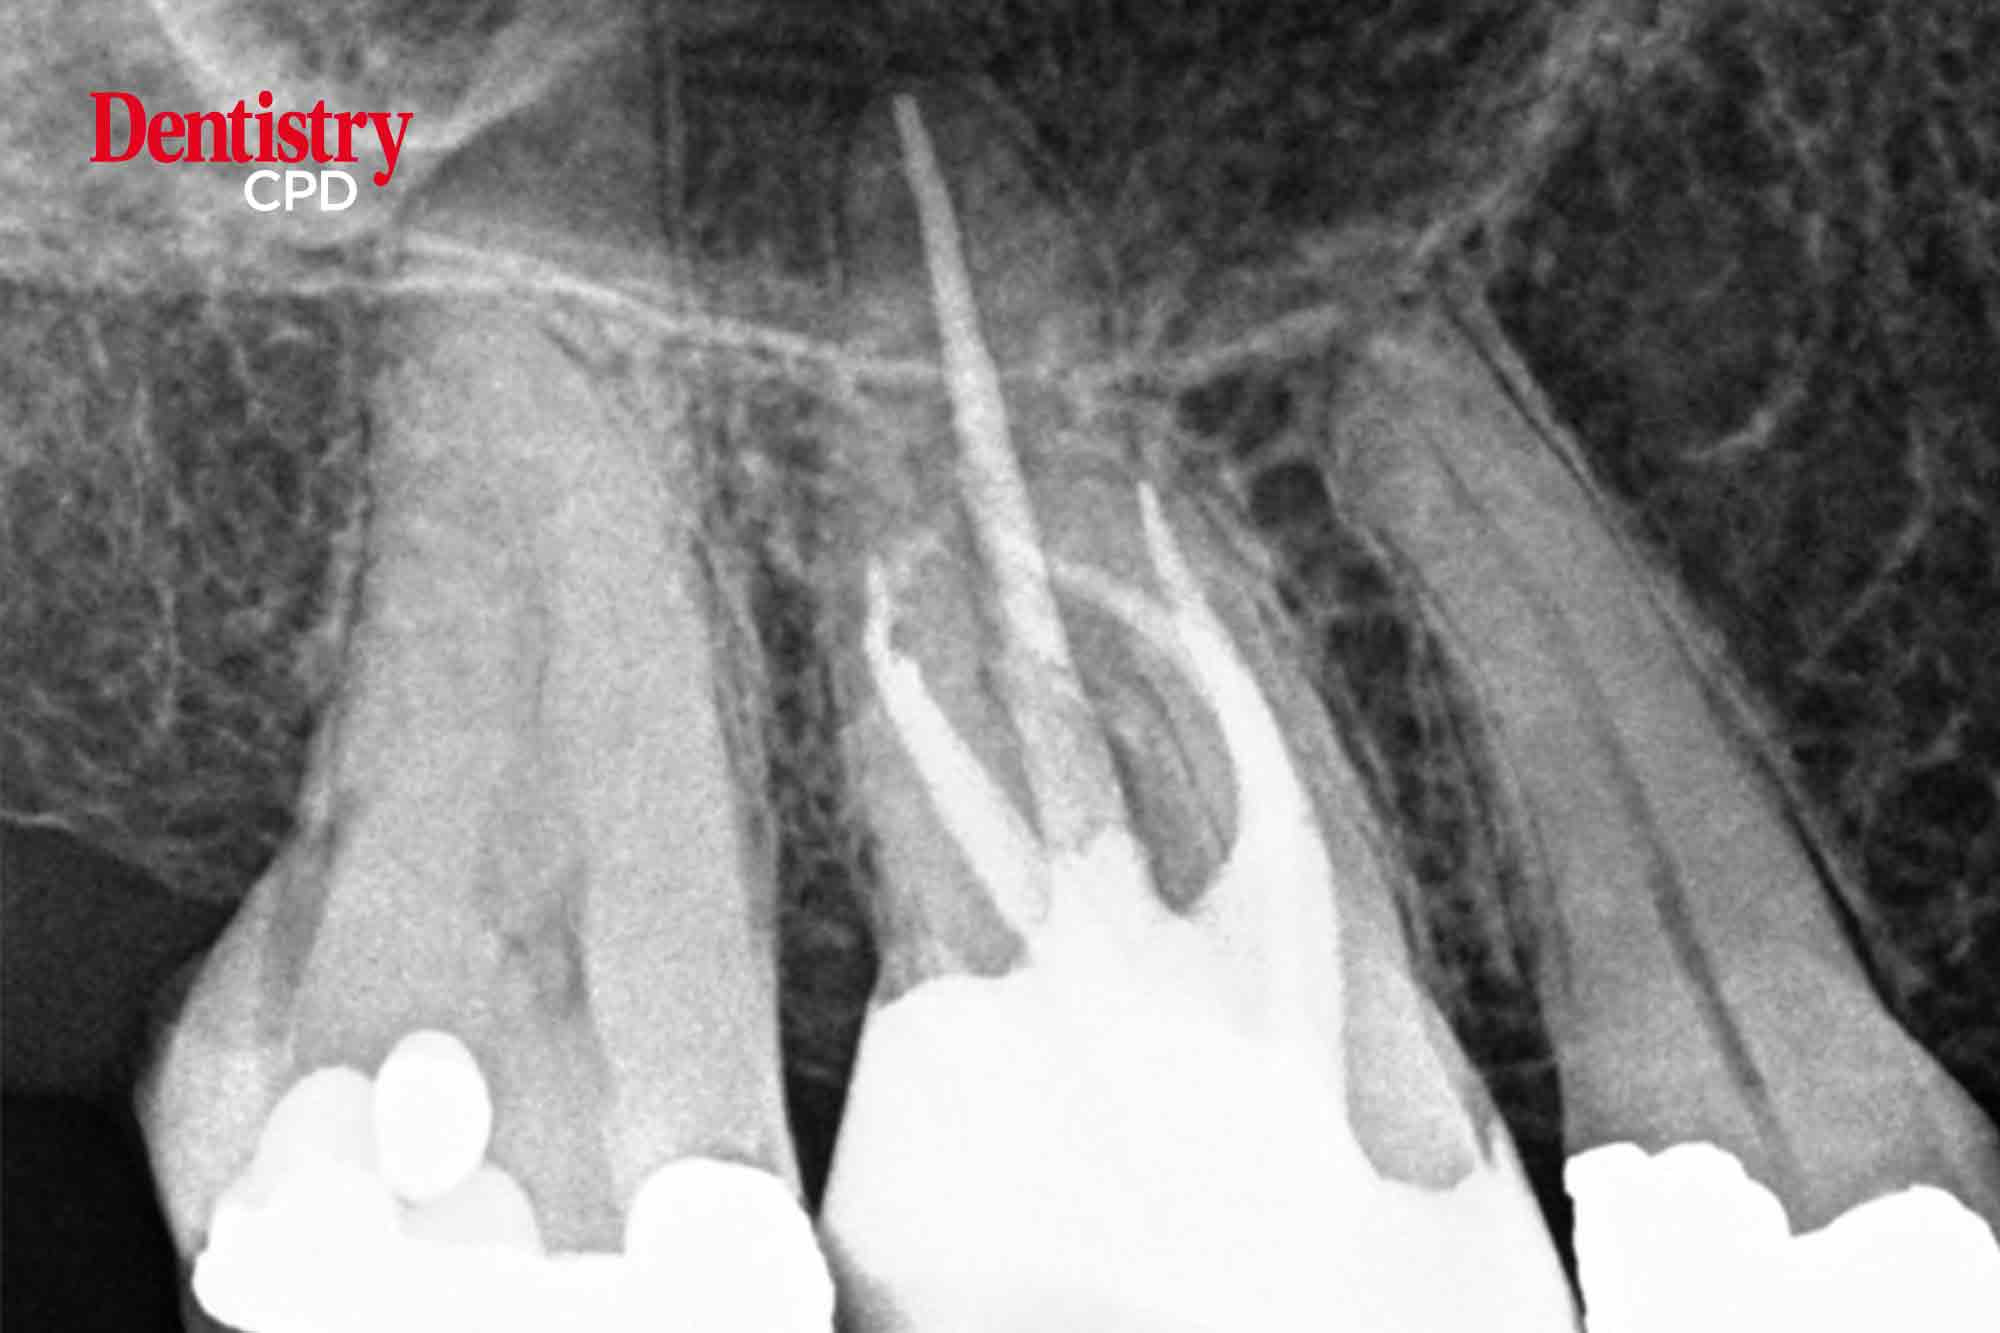

The MB2 or ‘fourth’ canal has a quite the reputation for being challenging to locate and negotiate. Kreena Patel discusses facts about the MB2 and clinical tips for successfully managing it